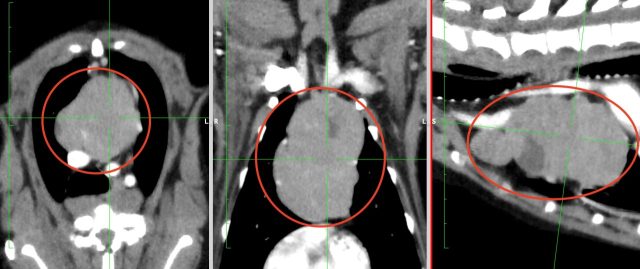

・CT検査:大きさや広がり、リンパ節転移、遠隔転移の評価、

※CT検査はより綿密な治療方針を決定するうえで推奨される検査です

胸腺腫のCT画像(赤丸)